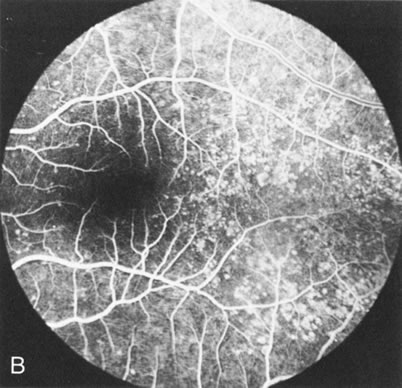

In retinitis pigmentosa (RP), the pigment abnormalities of atrophy, migration, and clumping are made apparent by transmitted hyperfluorescence and blocked hypofluorescence (Fig. 1A). Patients who have very minimal pigmentary alterations (pauci pigmentary RP) or no pigment abnormalities (RP sine pigmento) may show the abnormalities on fluorescien angiography (FA). It is uncommon to see choriocapillaris atrophy except in the late stages. This finding corresponds to the histopathology, which shows that the earliest abnormalities are in the photoreceptors and that the choroid is normal.1

Dye leakage in RP may occur from the retinal vessels or at the level of the retinal pigment epithelium (Fig. 1B).2–4 The leakage may be seen in the macula and posterior pole, along the vascular arcades in the distribution of the radial peripapillary capillaries, and in the periphery (where an exudative vasculopathy resembling Coats' disease is suggested).